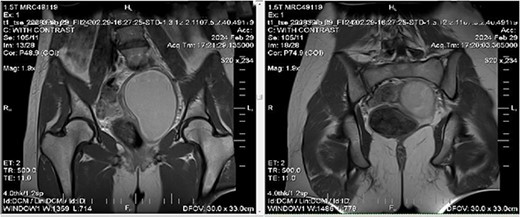

We ordered an MRI with contrast injection to assess the ultrasound findings, which showed a big pelvic cystic hematoma measuring (7 × 12 × 6.7 cm) in the left paracentral position that extends close to the vaginal opening to the level of the right adnexa, encircled by a regular, thick wall that did not luminesce, and a relatively small myometrium with a regular endometrium (Fig. 1). It also shows the level of vaginal obstruction (Fig. 2).

MRI imaging showing a big pelvic cystic hematoma measuring (7 cm × 12 cm × 6.7 cm) in the left paracentral position that extends close to the vaginal opening to the level of the right adnexa, encircled by a regular, thick wall that did not luminesce, and a relatively small myometrium with a regular endometrium.